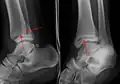

A triplane fracture of the ankle as seen on plain X-ray A triplane fracture of the ankle as seen on plain X-ray

- Triplane fractures are a special type of fracture that involves the immature skeleton. It has a coronal plane in the metaphysis, an axial plane in the physis, and a sagittal plane in the epiphysis.[15]